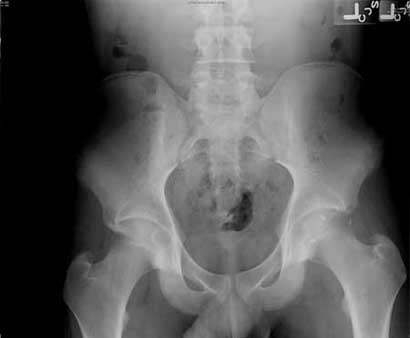

Left acetabular dysplasia with coxa valga and subluxation.